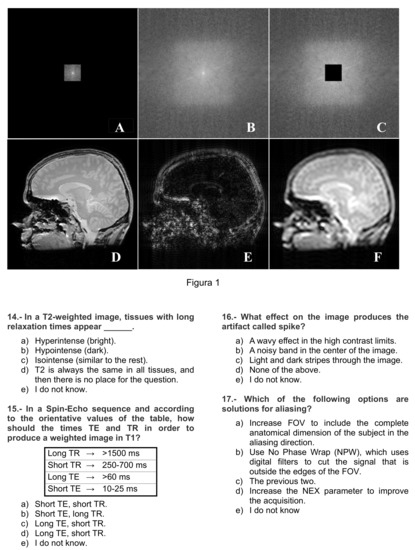

Figure A2.

Instrument page 2 of 4.

Appendix B shows the questionnaire translated into English. Each item has four possible answers together with the answer “I do not know”; the latter intends to avoid random answers. The first 10 items correspond to the content of the first lecture, as enumerated in Section 2.3, while the remaining items correspond to the content of the second lecture. Since the content of this first part deals with theoretical aspects of MRI and was presented in a purely explanatory way, we will hereafter refer to it as “theoretical” part or “T part”, while the second will be hereafter referred to as “practical part” or “P part”. The score of the questionnaire is the number of correct answers (hereafter referred to as “hits rating”); hence the maximum score is 10 points in each part. This score will be used by default. For the sake of completeness, a null-expectation version of the rating—random answering leads to an average zero score—has also been accounted for.